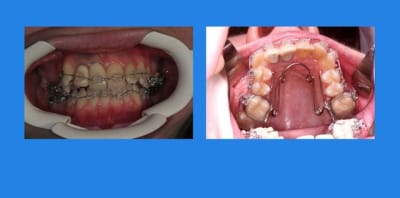

Début du cas :

pose mat Sup.

1 q4hjp9 - Eugenol

13/03/2010 à 23h42

4mois après, comme ça n’avance pas vite, pose Q.H

et pose du mat. Inf.

2 wqai8e - Eugenol